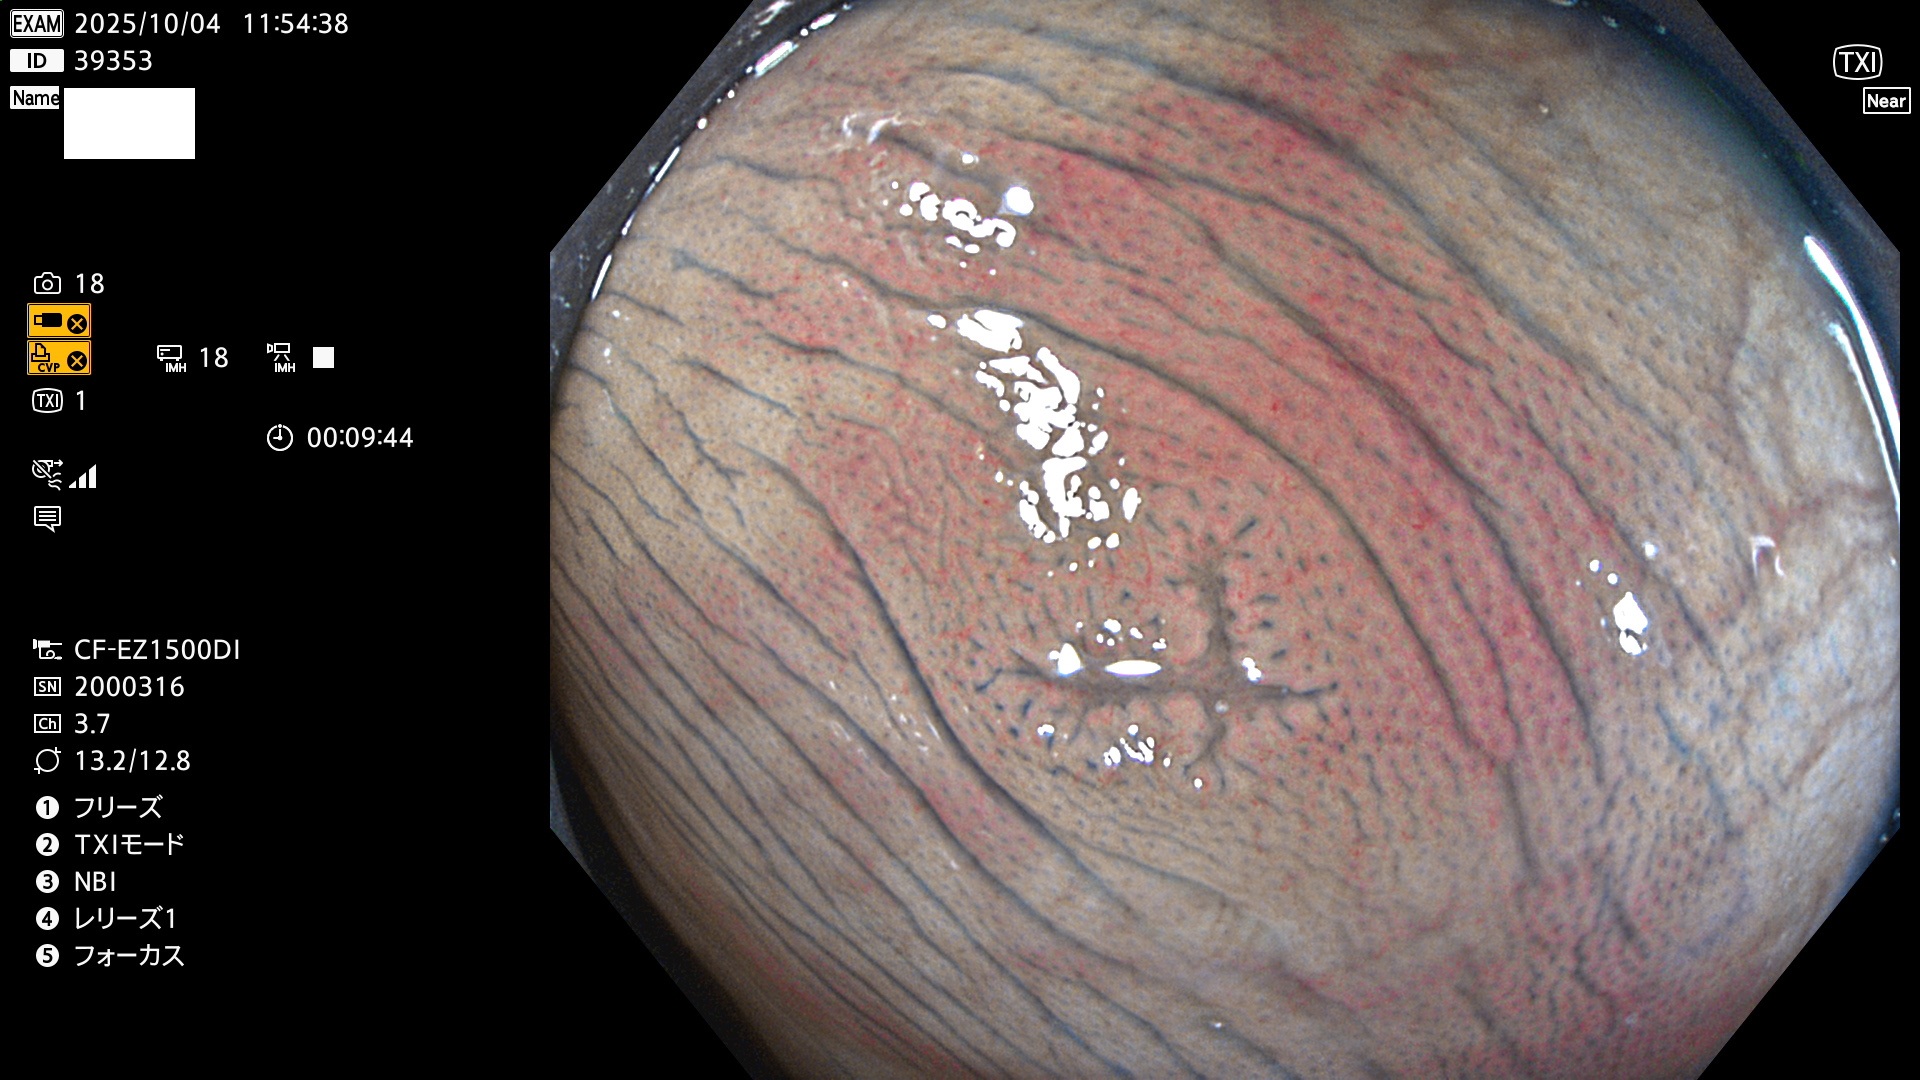

完全に平坦な物をUb、陥凹している物をUcと呼びます。Ubは認識が困難で、Ucはびらん(炎症)と紛らわしいために見落とされやすく、「内視鏡後・大腸癌」の原因になります。

専門的)Uc=De Novo癌? 内視鏡の解像度が低かった時代、このような説もありました。しかし今日の高精度内視鏡では良性の微小なUc型腺腫(APC遺伝子異常の腺腫)が日常的に見つかります。Ucこそが多段階発癌(Adenoma-Carcinoma Sequence)のMain Routeです。

毎週の検査(木・金・土・日)に発見されたUbとUc型・腺腫を、その週の日曜の夜にUPし1週間、提示します。

2025年10月2日〜10月5日の4日間(40件)で9個 (Uc_ADR=9個/40人=23%)